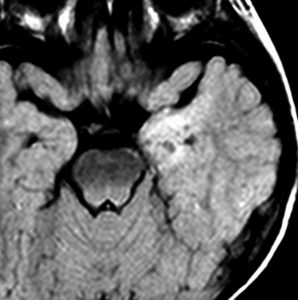

乳児期にてんかん発作で発症する内側側頭葉過誤腫

mesial temporal hamartomatous tumor

乳児期に全身性感帯痙攣発作で発症しました。左海馬鈎に強い石灰化があります。側頭葉硬化症とも言われるものです。この部位の過誤腫様の腫瘍は難治性てんかんとなることが多く,病変切除が必要となります。

脳波では前頭葉に蕀律動を認めます。切除は扁桃体と海馬鈎の摘出を目指すものです。